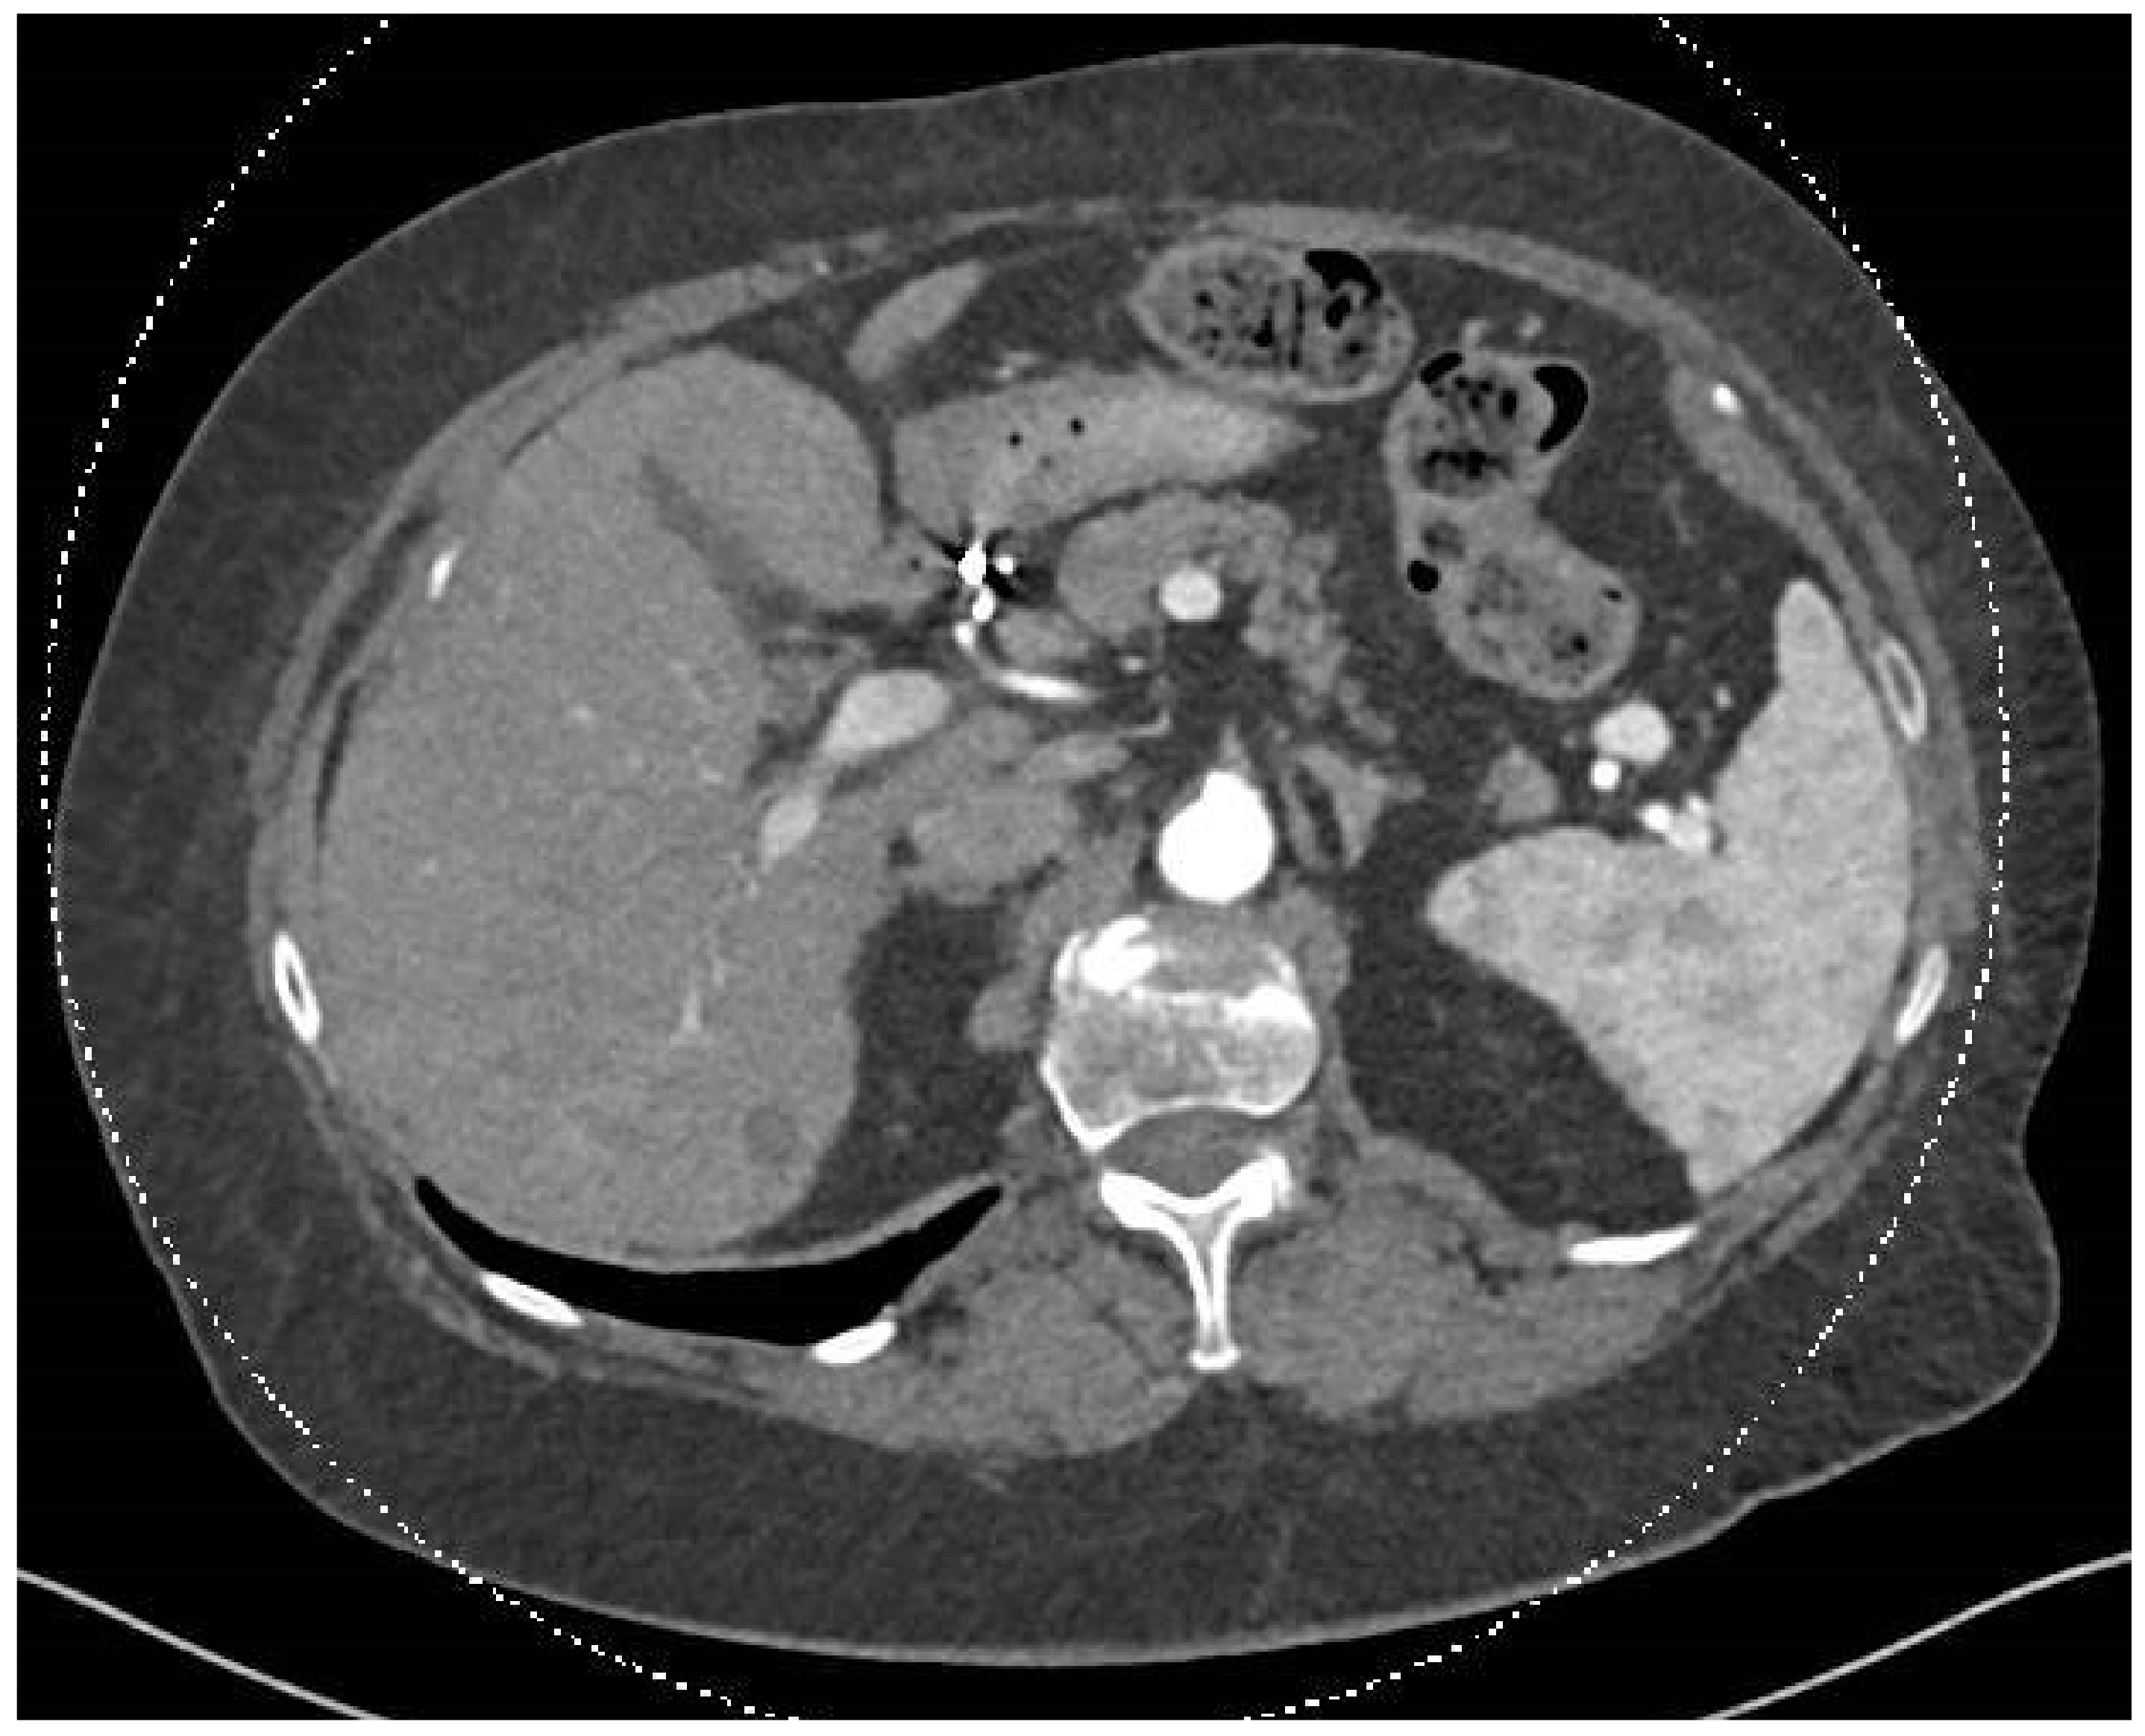

In December 2023, a full-body CT scan revealed that two known liver metastases had grown, and a new lesion had appeared near the inferior vena cava (IVC) in the liver. A multi-phase liver CT protocol performed later in December identified five lesions in the right liver lobe and at least one lesion in the left lobe (Figure 1). After consultation with an interventional radiologist, it was determined that the disease spread pattern was unsuitable for chemoembolization. Still, it was appropriate for selective internal radiation therapy (SIRT) using Yttrium-90. In February 2024, approximately one week before SIRT treatment, the patient underwent preparatory hepatic catheterization and selective simulation using Tc-99mma, demonstrating the feeding arteries to the liver tumors, and a low lung shunt fraction of 9% was calculated. During this preparatory hepatic catheterization simulation, the arteries feeding the tumors were mapped, allowing optimal catheter location placement (Figure 2). On 8 February 2024, the SIRT procedure was conducted under general anesthesia due to the patient’s back pain and inability to lie flat; a puncture was performed under local anesthesia, with fluoroscopy and ultrasound guidance, in the right common femoral artery. Catheterization of the superior mesenteric artery (SMA) was performed, and pressure injection showed no vessels from the SMA supplying the tumor. Subsequently, catheterization of the celiac artery was performed, with automatic injection showing celiac artery anatomy and pathological tumor enhancement in both liver lobes, particularly in the right lobe. A branch from the common hepatic artery was identified, supplying part of the right liver lobe, including at least two tumors. An accessory branch to the left lobe was observed through the left gastric artery, though it did not supply the liver tumors. Three doses of technetium were injected selectively into the right hepatic artery distal to the cystic artery, the left hepatic artery and a branch supplying part of the tumors in the right lobe, which originates from the proximal common hepatic artery. Due to the proximity of the origin of the right gastric artery, embolization with 2 mm coils was performed. At the end of the scan, the patient was transferred to the Nuclear Medicine Department, which showed a minimal lung shunt (9%) with no evidence of gastrointestinal shunt. The patient was then returned to the angiography suite for the second phase of the procedure. Selective catheterization of the three arteries was repeated, and technetium was injected with a total calculated dose of 1.4 GBq (0.4 to the left lobe, 0.4 to the systolic artery in the right lobe, and 0.5 to the right hepatic artery distal to the cystic artery). SIRT treatment was performed successfully with no apparent complications, and the patient was discharged home the next day.

Figure 2.

This CT angiography, performed on 8 February 2024, simulates contrast injection, highlighting the blood supply to the tumors during the arterial phase.